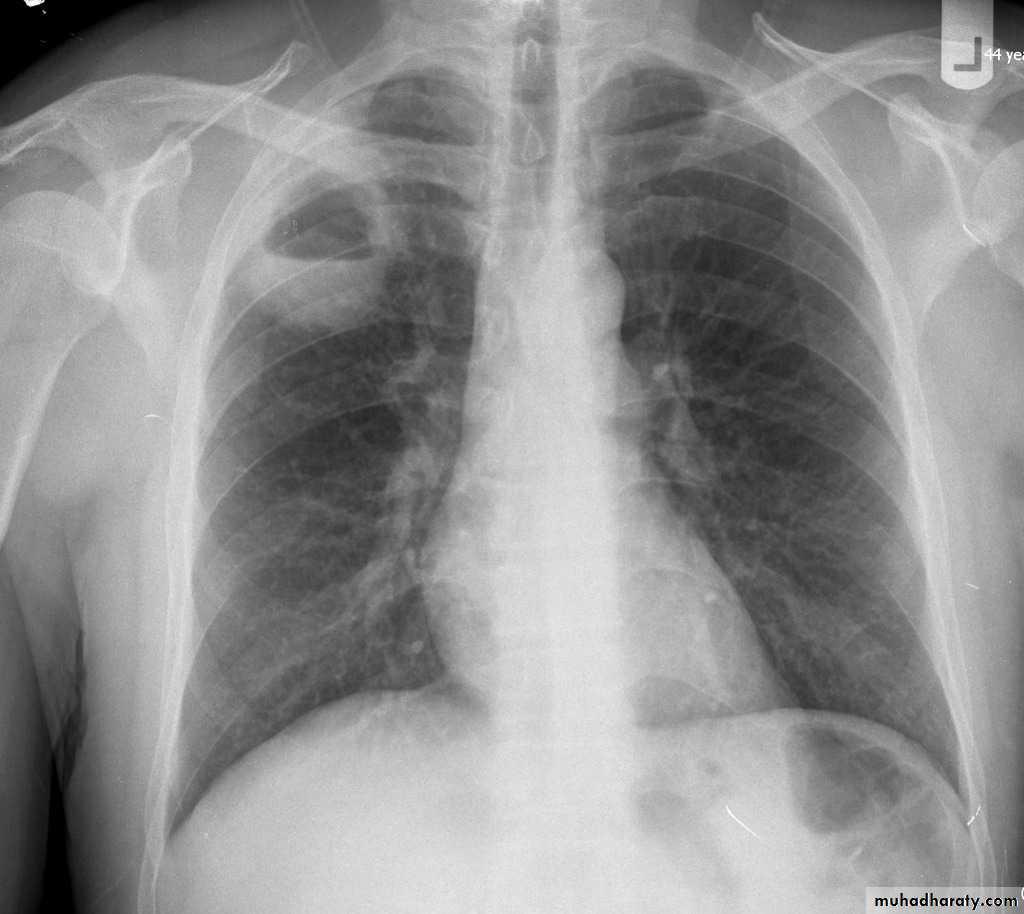

Bronchiectasis

59.Bronchiactasis